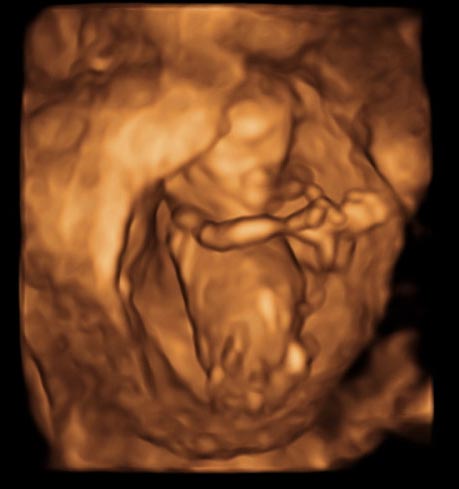

初めまして 12週4日の3dエコーの写真です この写真で見る Yahoo 知恵袋

質問 Itmedia 3d画像の性別判断にご協力ください

この3dエコー写真から 性別判断は難しいですか この角度では 男の子 Yahoo 知恵袋

3dエコー性別について 現在妊娠13週の妊婦です こちらシンボルのようなもの Yahoo 知恵袋